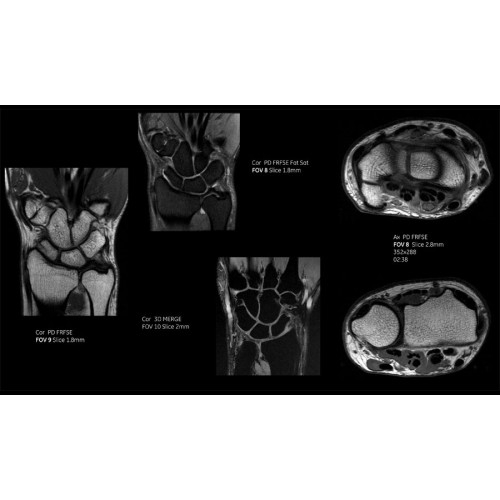

Детализация изображений

Система SIGNA Pioneer воплощает поразительные достижения в области визуализации. Передовая технология Total Digital Imaging (TDI) позволяет добиться большей четкости изображений и на четверть повысить соотношение сигнал/шум.

TDI построена на трех базовых компонентах:

• Технология Direct Digital Interface (DDI) использует независимый аналого-цифровой преобразователь для оцифровки сигнала от каждого из 97 радиочастотных каналов, что обеспечивает значительное увеличение качества за счет уменьшения фонового шума.

• Технология Digital Micro Switching (DMS) — это следующее поколение технологий радиочастотных катушек, основанное на замене аналоговых схем блокировки сверхбыстрыми микропереключателями (MEMS), что делает возможным быстрое переключение катушек для дальнейшего расширения возможностей визуализации с нулевым TE.

• Технология Digital Surround Technology (DST) — это новая технология объемной оцифровки данных, объединяющая сигналы от каждого элемента катушки. Прекрасное соотношение сигнал/шум и чувствительность поверхностных катушек в сочетании с превосходной однородностью и высокой проникающей способностью встроенной радиочастотной катушки — все это позволяет создавать качественные изображения не только позвоночника, но и всего тела.